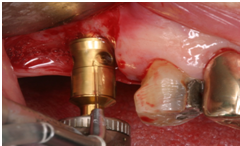

於100/06/07重新放置兩顆植體

並於100/10/25將中間兩顆植體做二階接出

由於前後植體的高低差距太大,決定將中間兩顆高度較為一致的植體假牙做連結,但前後兩顆做單顆假牙的設計。